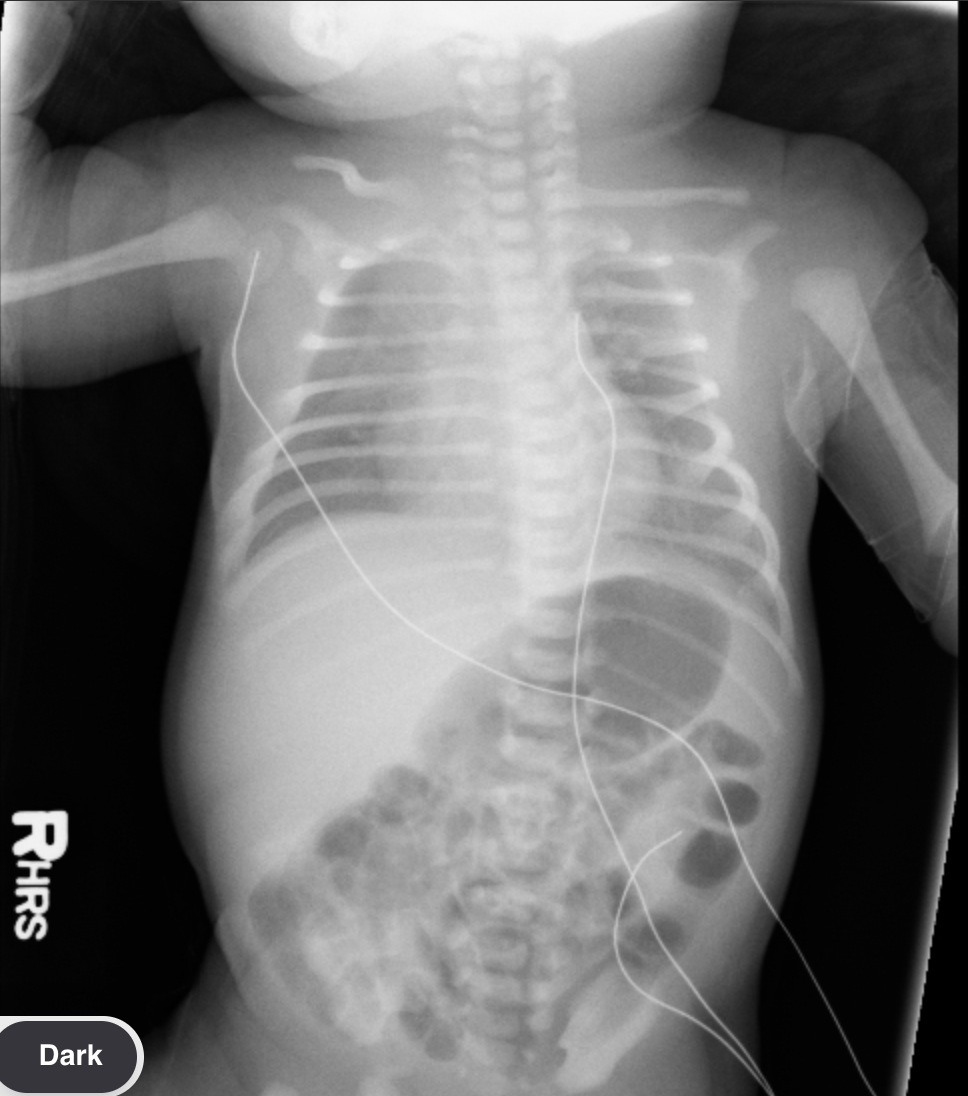

Pulmonary Interstitial Emphysema

• Ventilation in patients with surfactant deficiency causes alveoli to pop and air to escape

• Bubbly or linear lucencies

• Imaging findings seen at first week of life

• <4 weeks old (note BPD >4 weeks old)